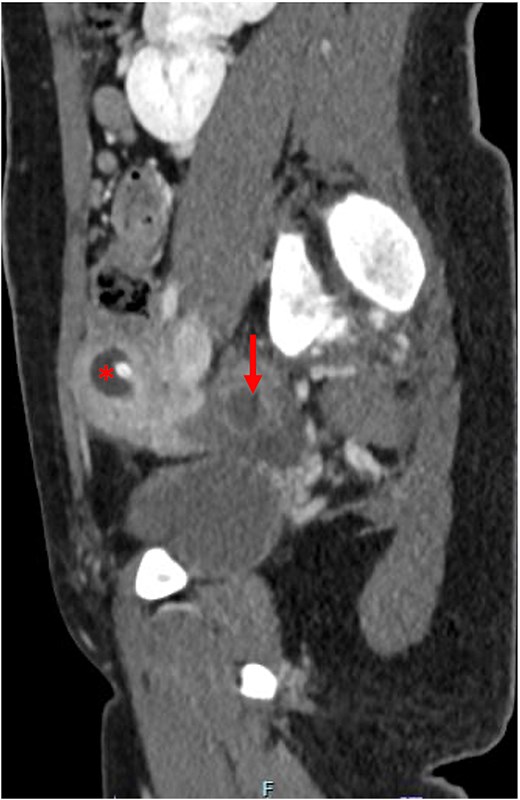

An abdominal ultrasound was done to rule out appendicitis and showed free fluid in the right lower quadrant. A follow-up pelvic ultrasound showed a complex right adnexal cystic structure. A computed tomography abdomen/pelvis (CT AP) was performed and showed an abnormally positioned uterus in the right hemipelvis with hematometra, no identifiable cervix, a right adnexal cystic structure measuring 3.7 cm, free fluid in the pelvis, and a supernumerary right kidney fused to the native right kidney. This constellation was suggestive of a Mullerian duct anomaly. Pelvic magnetic resonance imaging (MRI) demonstrated a right unicornuate uterus with hematometra with an absent left horn, a right dilated hematosalpinx measuring 3.8 cm, a left ovary displaced to the anterior left lower quadrant, cervical aplasia, and vaginal atresia consistent with a Mullerian duct anomaly (U5a C4 V4) (Fig. 1).

(a) Pre-operative axial computed tomography imaging, demonstrating a right uterine horn with hematometra (*) and a right adnexal cystic structure representing hematosalpinx (arrow). (b) Pre-operative pelvic parasagittal T2 weighted MRI, demonstrating a right uterine horn with hematometra (*), a right adnexal cystic structure representing hematosalpinx (arrow), normal right ovary (o), cervical aplasia, and vaginal atresia (arrowheads). (c) Pre-operative pelvic axial T2 weighted MRI, demonstrating a right uterine horn with hematometra (*), and a right adnexal cystic structure representing hematosalpinx (arrow). (d) Pre-operative abdominal axial T2 weighted MRI, demonstrating a right supernumerary kidney (arrow).